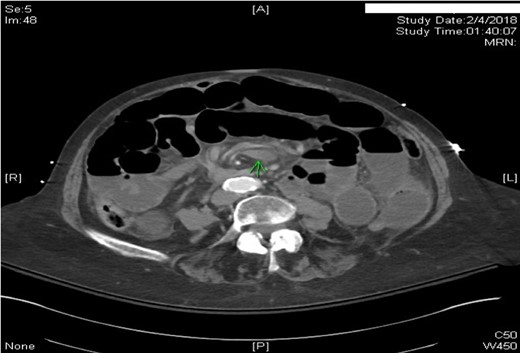

This case report presents an 80-year-old female with past medical history of Marfan syndrome with extensive cardiovascular manifestations including coarctation of the aorta, mechanical aortic valve and mitral valve replacement, heart failure with reduced ejection fraction (25–30%), and atrial fibrillation. The patient was admitted to the emergency general surgical service for complaints of acute onset colicky periumbilical abdominal pain, progressive abdominal distension, nausea and vomiting for 2 days. Emesis was described as non-bloody and non-bilious. Other pertinent history included one bowel movement 12 h prior to admission, which was non-bloody and inability to pass flatus for more than 24 h. No previous episode of abdominal pain of similar nature were elicitated. Physical examination was significant for mild abdominal distension and generalized tenderness to palpation in all quadrants without signs of peritonitis. Patient was afebrile and hemodynamically stable. Significant laboratory findings were INR of 2.20 (on warfarin for valve replacement), hyponatremia of 125, acute kidney injury with creatinine of 1.56. computed tomography (CT) of the abdomen/pelvis was significant for high-grade small bowel obstruction with a swirling of the superior mesenteric artery (SMA) and superior mesenteric vein (SMV) suggesting rotation of intestinal mesentery (Fig. 1) [5]. The SMV was located to the right of SMA, a reliable finding against intestinal malrotation [5] (Fig. 2). Further, there was no radiologic evidence of malrotation like transposition of SMA and SMV, the horizontal part of the duodenum not reaching medioventral line, and malposition of ileocecal junction [5]. The INR was not reversed with FFP and Vitamin K due to concern for stroke. Emergent exploratory laparotomy within 6 h of admission was performed which was significant for midgut volvulus with the small bowel rotating around the base of mesentery a complete 360°. There were no signs of ischemia, and hence manual untwisting of the bowel was performed [2, 5]. The cecum was noted to be on the right lower quadrant and ligament of Treitz was on the left upper quadrant. The small bowel mesentery was noted to appear long with narrow base and floppy likely contributing to hypermobility of the small bowel. The patients postoperative course was uneventful, and she was discharged to skilled nursing facility for further rehabilitation.

Axial CT scan of abdomen with IV contrast. SMV was located to the right of SMA.